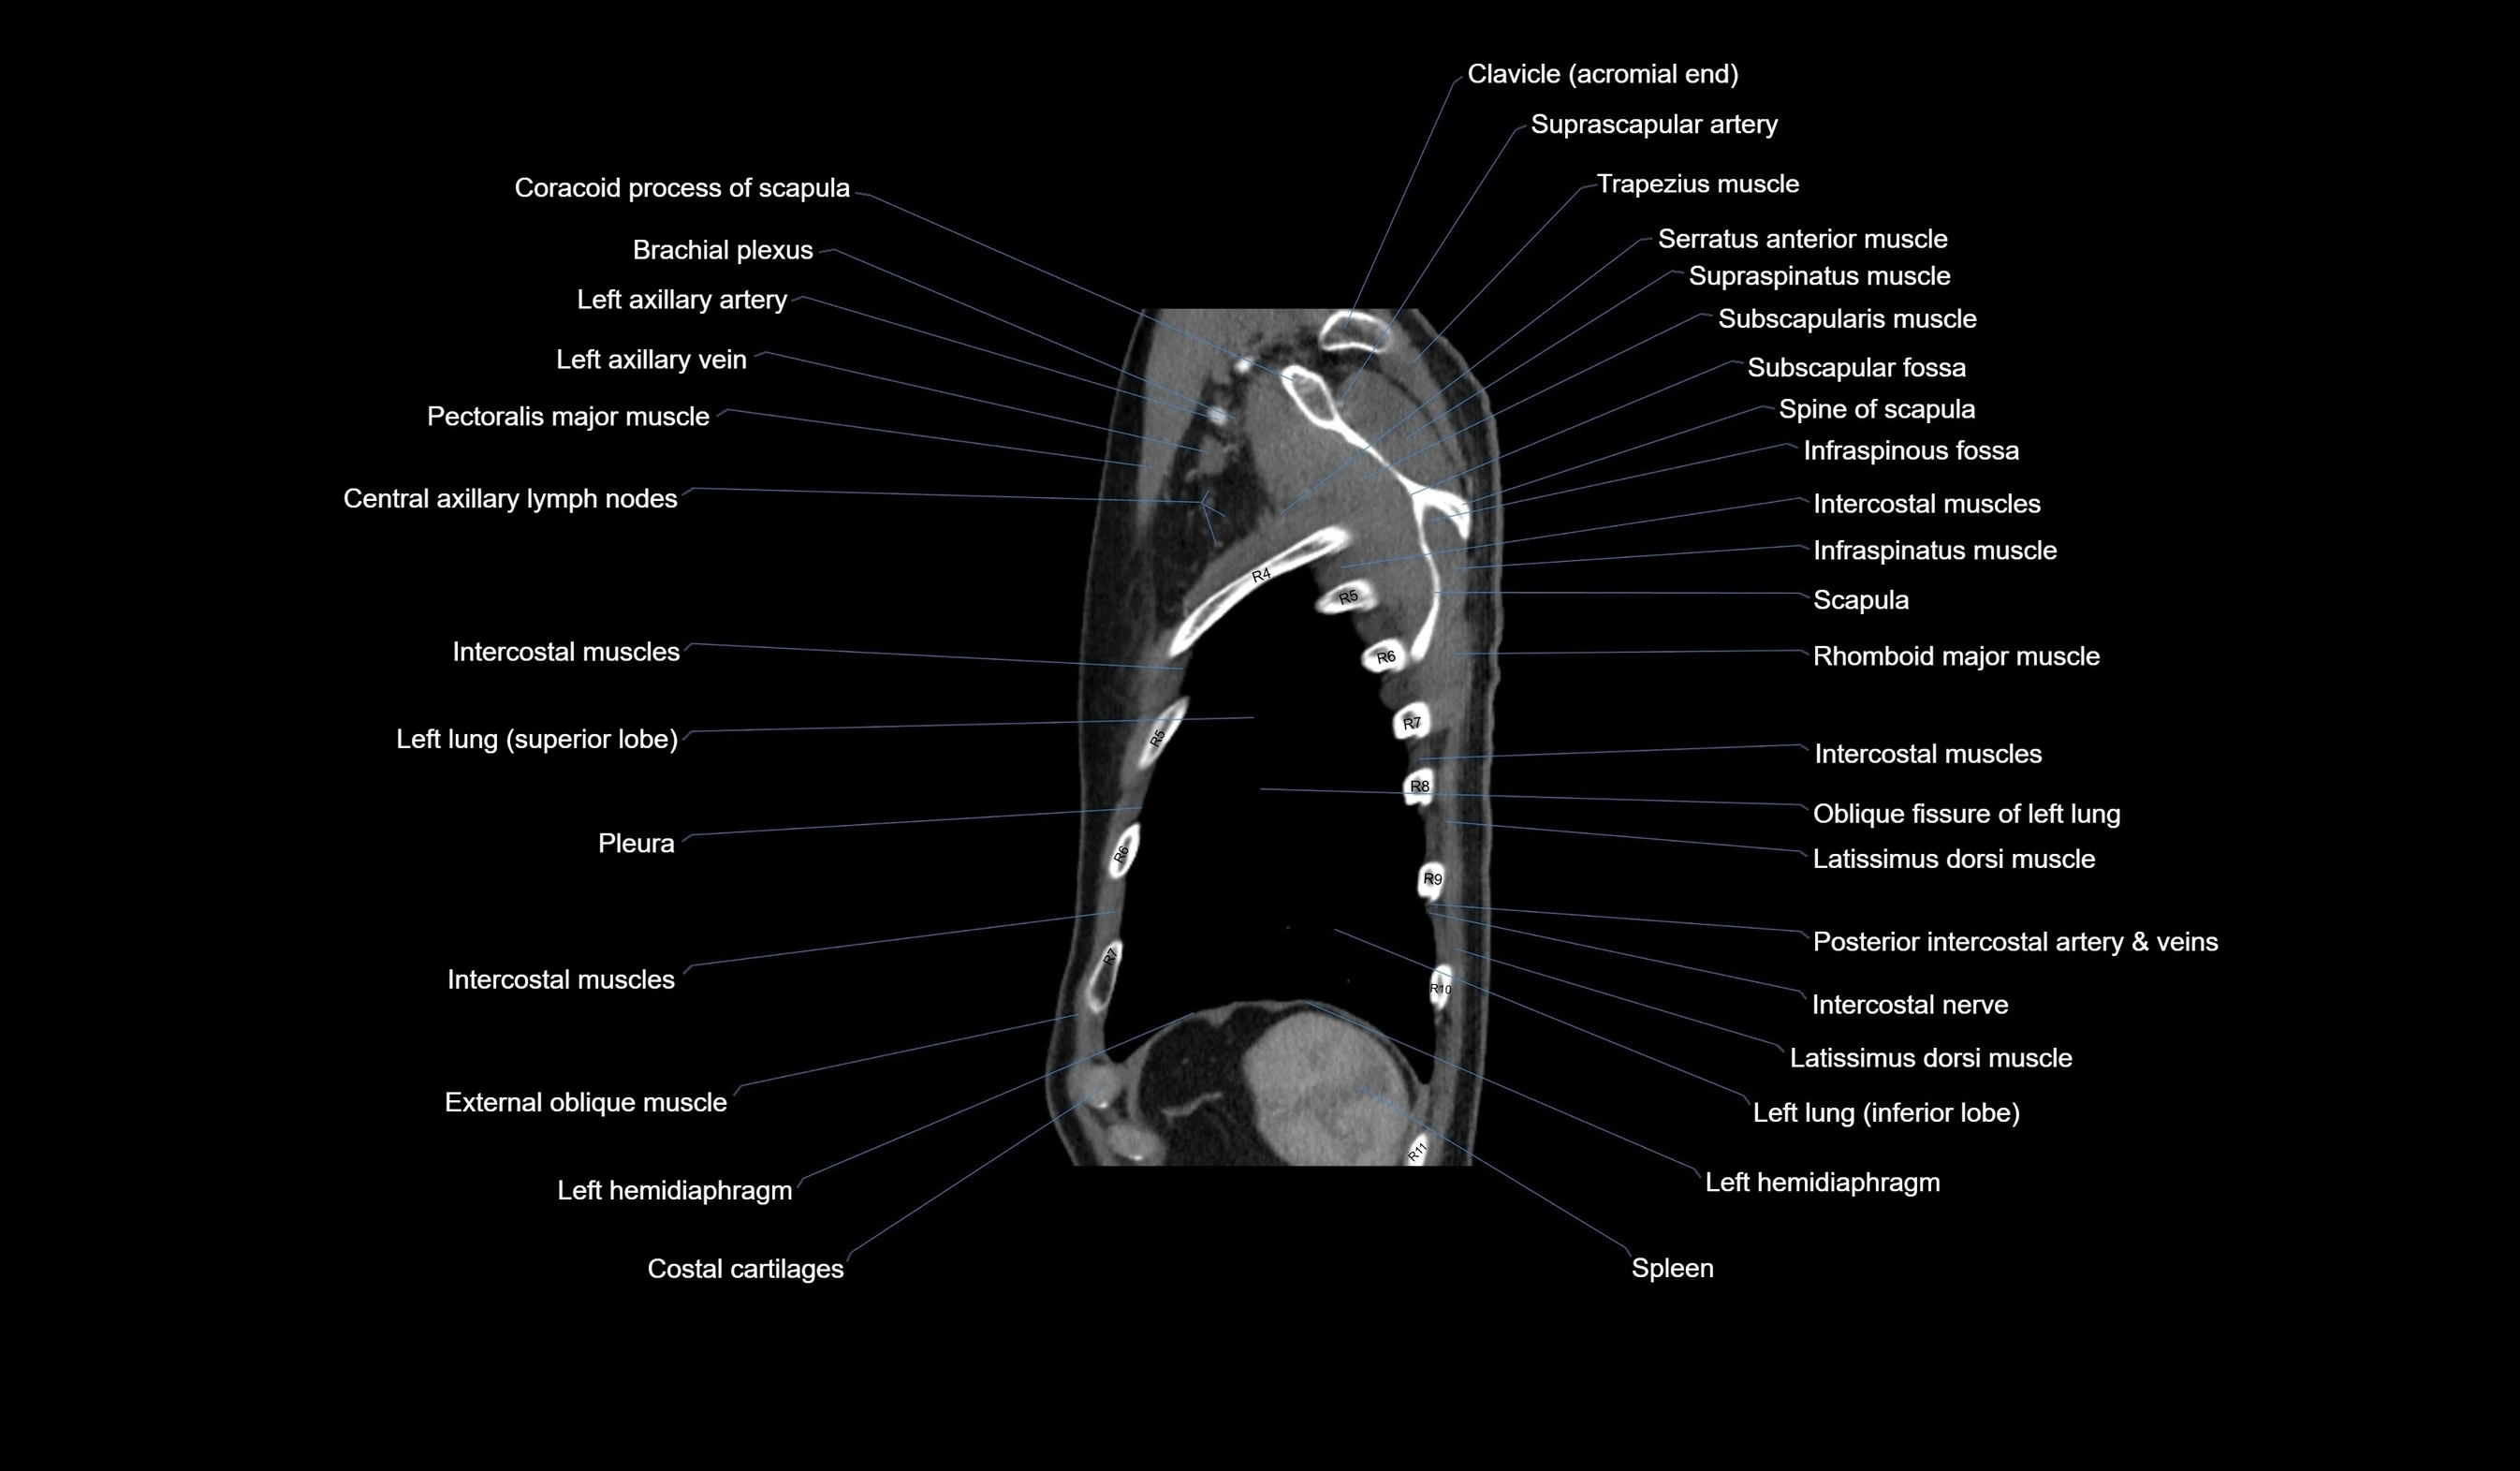

- Scapula

- Spine of scapula

- Infraspinatus muscle

- Intercostal muscles

- Latissimus dorsi muscle

- Oblique fissure of left lung

- Spleen